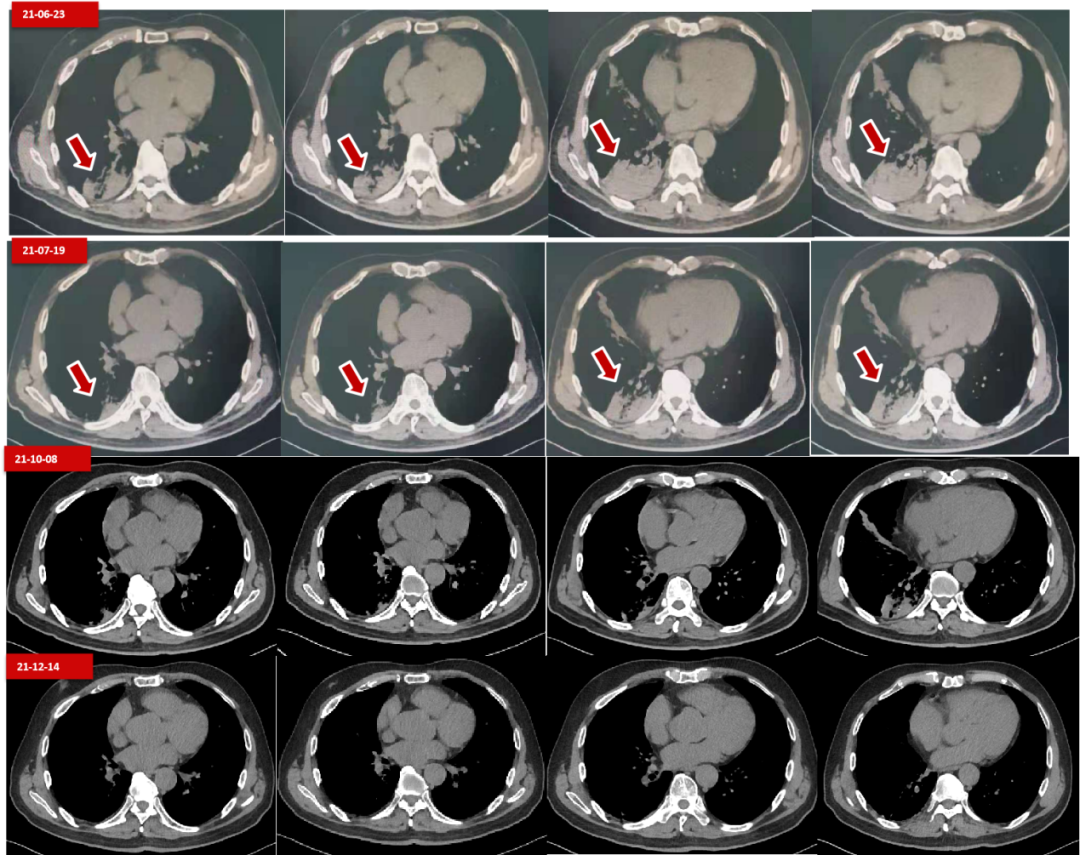

一眼洞穿系列之——一例肺部肿瘤从小到大再扩散的三次ct对比

多次进展仍获得超5年长生存,这例braf突变晚期肺癌患者是如何做到的?